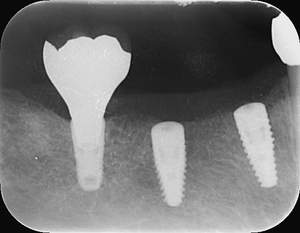

レントゲン写真

- 透過像

| 治療方針 | 右下の当該歯は歯根破折により保存不可能と診断しました。歯周疾患も伴っていたため抜歯後に骨吸収※1が大きく起こることが予測できました。チタンメッシュ併用骨再生誘導法(GBR※2)を選択しインプラント埋入と同時に行い自然な歯槽骨のラインを再現しました。またGBRを行う際にインプラント辺縁の付着歯肉の減少が起こる為、遊離歯肉移植術(FGG※3)を行い清掃性を考慮した形態に仕上げました。 ■治療方針の解説 治療した右下の歯をレントゲンで撮影したところ根本の部分に黒く写る箇所があり「根尖性慢性周囲炎※1」と診断。また歯周病も進行していました。 ※1 骨吸収・・・歯槽骨という歯を支える骨がなくなっていくこと |